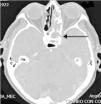

La tomografía axial computarizada contrastada mostró aumento de volumen del seno esfenoidal izquierdo con erosión y defecto de la pared ósea e invasión al seno cavernoso del lado izquierdo, asociado a pansinusitis ipsilateral (fig. 3).

Los hallazgos radiográficos característicos son demostrados a menudo mediante tomografía axial computarizada como una lesión expansiva llena de líquido mucoide de densidad homogénea delimitada por una seudocápsula y no por el límite óseo que en ocasiones ya no existe debido a la erosión. Al aplicarse medio de contraste, esta pared acumula en forma anormal el contraste y el líquido interno de la lesión no muestra cambios. En la resonancia magnética se observa una señal de baja intensidad en las secuencias T1 y alta intensidad en T2, debido al gran contenido líquido del mucocele, pudiendo predecir la cronicidad de la lesión cuando en ambas secuencias se observa una señal de intensidad media a alta por aumento de material proteinaceo en el interior de la lesión. Asimismo la resonancia es útil para realizar diagnóstico diferencial con lesiones malignas o de comportamiento atípico9.